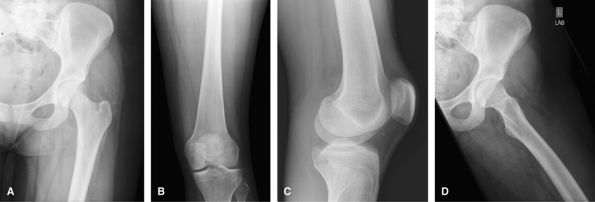

![]() |

Figure 28 (A) AP. (B) Mediolateral lateral.

Trauma, Acute Injury

Shoot through lateral added to assess for a

lipohemarthrosis, if present a fracture must be sought. CT is a useful

adjunct to assess for occult tibial plateau fractures and to plan

surgery with fractures seen on radiographs. MRI being used increasingly

to assess accompanying soft tissue injuries in cases of tibial plateau

fractures.

Figure 29 (A) AP. (B) Mediolateral lateral. (C) Lateromedial crosstable lateral.